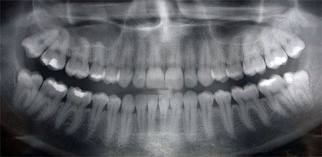

คุณต้องทำนัดเข้ามาพบคุณหมอเพื่อให้คำปรึกษา และตรวจฟันก่อน ถ้าหากคุณตกลงจัดฟัน คุณหมอจะพิมพ์ฟันเพื่อเก็บข้อมูลละเอียดก่อนเริ่มต้นการรักษา พร้อมกับ X-ray และเริ่มต้นเคลียร์ช่องปากจนเสร็จ

X-Ray กระโหลกศรีษะเพื่อการจัดฟัน และการตรวจช่องปากทั้งฟัน กระดูกขากรรไกร ข้อต่อขากรรไกร โพรงอากาศใต้โหนกแก้ม โพรงจมูก และกระดูกคอ เพื่อใช้ประกอบการจัดฟันและการรักษาอื่นๆที่ต้องการ